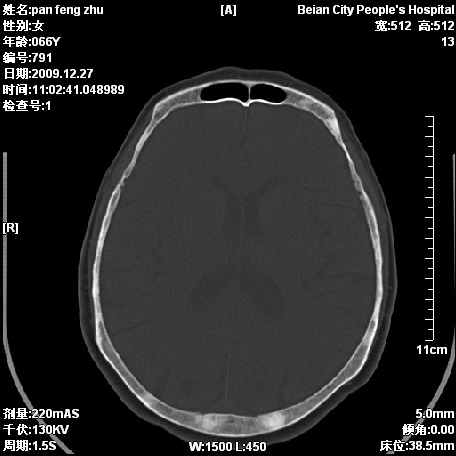

标题: CT23809:请会诊,头痛,66岁,女性。

核磁 t1和t2都是低信号

核磁 t1和t2都是低信号,并ct上呈圆形高密度影,理论上支持成骨转移。实质工作中不曾见过。

老年病人,成骨性骨转移瘤要考虑。骨斑点症不除外

好病例,几种考虑:转移,骨斑点症,骨髓瘤。

支持成骨性骨转移瘤。骨斑点症不考虑,骨髓瘤女性少见,且年龄太大。

支持成骨性骨转移瘤,建议进一步查原发灶。

颅底骨板如何 畸形性骨炎静止修复期?